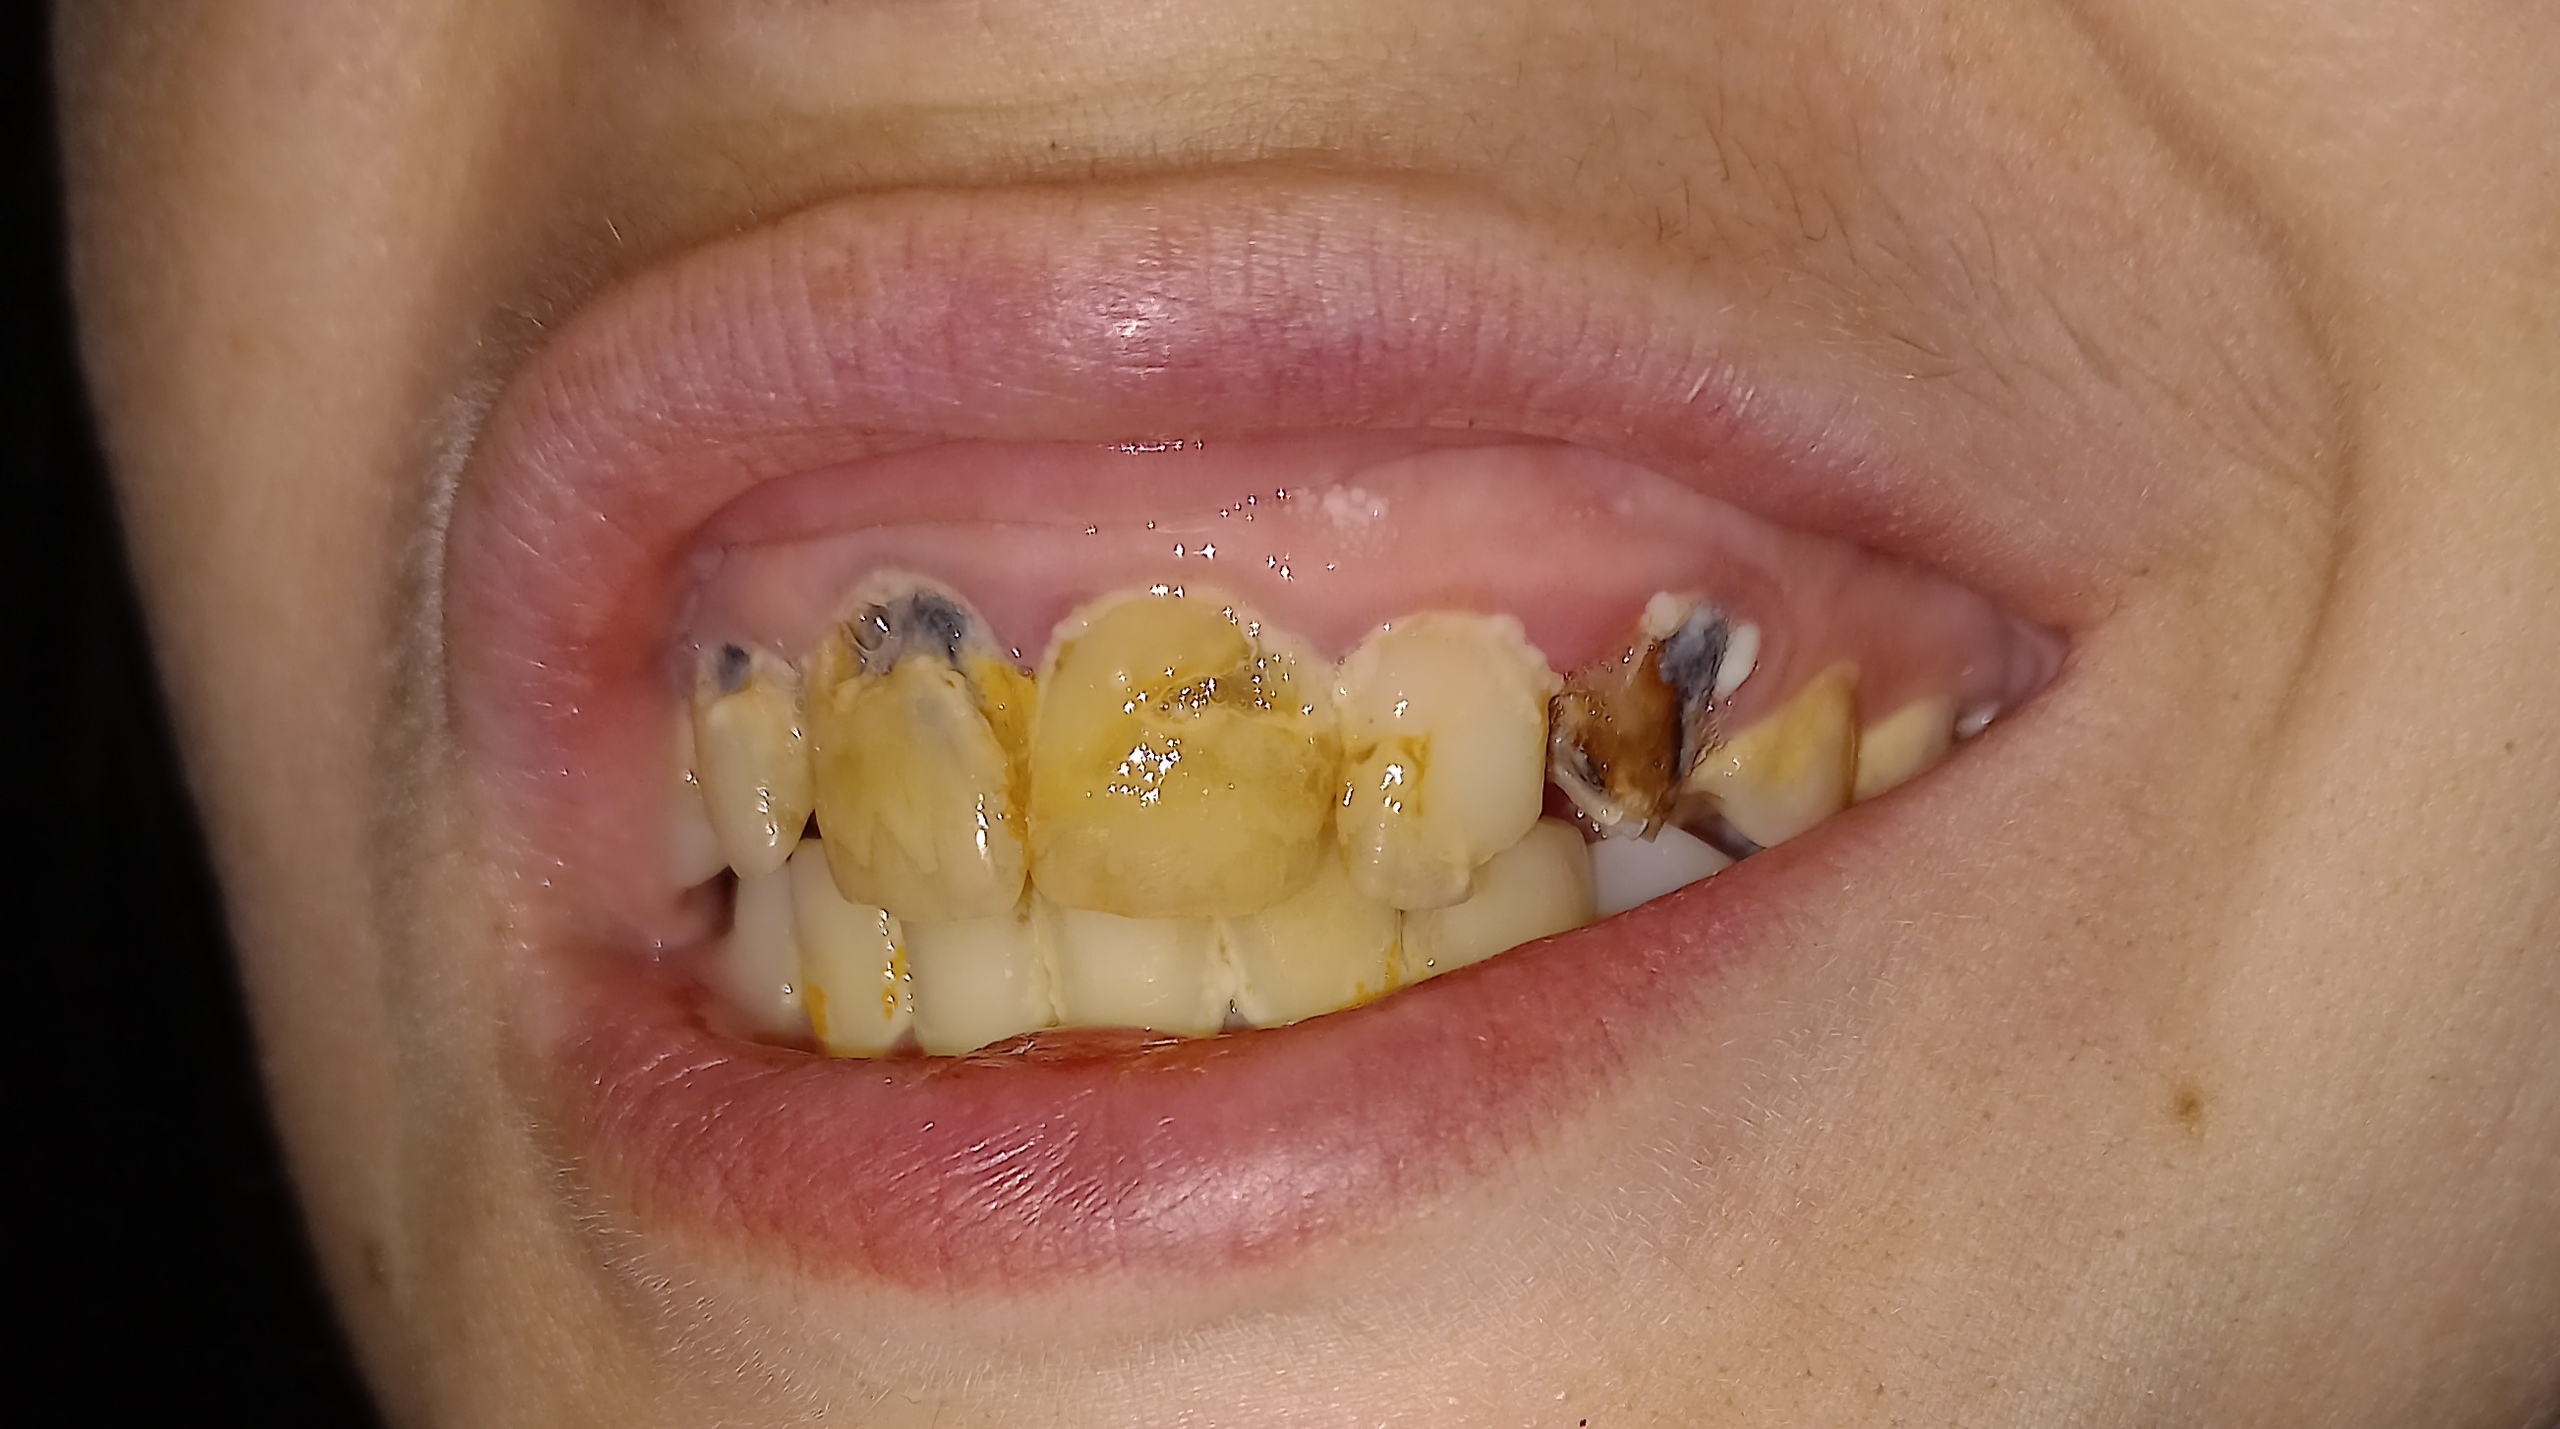

2.jpg 357Кб, 2560x900

2560x900

1.jpg 788Кб, 2560x1429

2560x1429

Двачь помогачь.

Есть одна ебанутая, довела зубы до такого состояния. К доктору идти боятся.

Собственно вопрос, можно ли туда хуй совать что можно сделать в домашних условиях. Она ведёт эталонный нищенский хиканский образ жизни, возможет ли это быть результат диеты или "плохой" воды? Зубы чистить не умеет, но не думаю что если научится, это сильно изменит ситуацию.